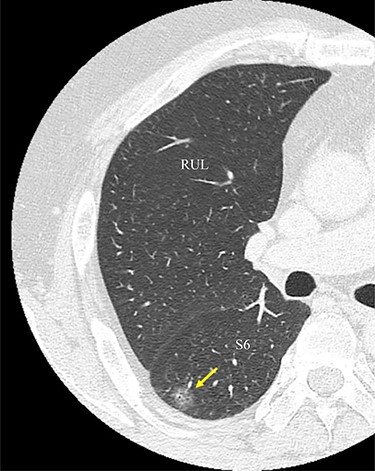

An image from CT scan taken in the axial plane. The tumor is located in the S6 of the right lung (arrow). RUL, right upper lobe; S6, superior segment.

A 56-year-old man was referred to our department for a right lower ground-glass nodule (GGN). Computed tomography (CT) revealed a pure GGN measuring 12 mm in diameter in the S6 of the right lung (Fig. 1). A pathological diagnosis could not be determined via transbronchial tumor biopsy. Three months after the initial investigation, CT revealed that the GGN had not shrunk, and a highly differentiated adenocarcinoma was strongly suspected. No hilar or mediastinal lymph nodes, or other organ metastases were observed on positron emission tomography/CT, or contrast-enhanced magnetic resonance imaging of the brain. Preoperative 3D CT revealed an aberrant A7b branching from the basal pulmonary artery (PA) and running behind the V6 (Fig. 2). The A7a and A7b subsegmental pulmonary arteries were located on the ventral and dorsal sides of the basal vein, respectively. Because lung cancer was highly suspected, surgery was scheduled.